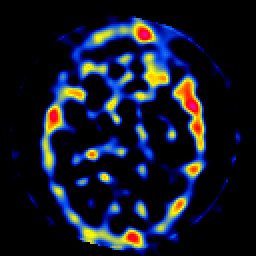

SPECT TL Study #8 -- Slice #24